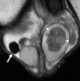

Postinflammatory scrotal pearl